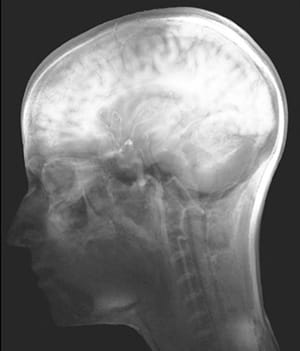

According to James Elkins, visual culture has superseded the practice of more traditional fine arts, thereby making ordinary visual information like medical X-rays, graphs, charts and advertisements fodder for artistic practice. In their two-floor exhibition at the new MUSECPMI (CPMI stands for Center of Photography and the Moving Image), Baysa and Hardy traverse these distinctions by presenting multifaceted representations of the brain.

The show negotiates two modes of interpretation. The first deals with the more traditional imaging of the brain’s soft matter and skull, in the Heideggerian sense of the thing as it is (i.e. this is your brain). An example of this is Hugh Hayden’s “Untitled” (2012) skull with soft dreads. The second interpretation presents the brain as we imagine it (i.e. this is your brain on drugs, as represented in the 1980s anti-drug commercial by a frying egg.) This mode of analogy allows for a wide range of representations of cognition and perception.